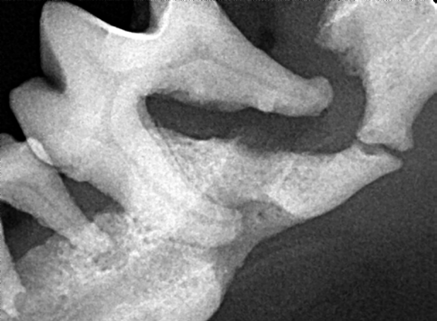

Les conséquences loco-régionales de la maladie parodontale les plus graves sont associées aux destructions osseuses survenant lors de parodontite avancée. Chez les chiens de petite taille le capital osseux (mandibulaire ou maxillaire) autour des racines dentaires est faible, l’ostéolyse liée à la maladie parodontale peut donc engendrer une fragilisation osseuse aboutissant à une fracture pathologique de la mandibule : souvent au niveau de la canine ou de la racine mésiale de la carnassière mandibulaires (figure 2a et 2b).

Figure 2a : maladie parodontale de stade terminale en région mandibulaire G chez un Bichon pesant 4 kg

Figure 2b : radiographie dentaire de la mandibule G du même chien qu’en 2a montrant une ostéolyse alvéolaire majeure sur la racine de distale de la M1 associée à une fracture mandibulaire pathologique

Face à une telle situation, le praticien se doit de réaliser un examen radiographique précis avant d’envisager l’extraction chirurgicale délicate de la ou des dents en cause puis réaliser un curetage de la zone infectée, tout en veillant à ne pas provoquer de dommages osseux supplémentaires (figure 2c).